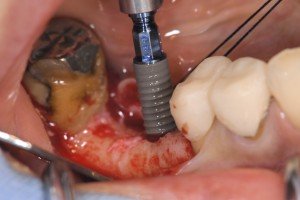

Straumann SLActive Roxlorid親水性サーフェイス埋入中です。

ロキソリッドSLActiveです。